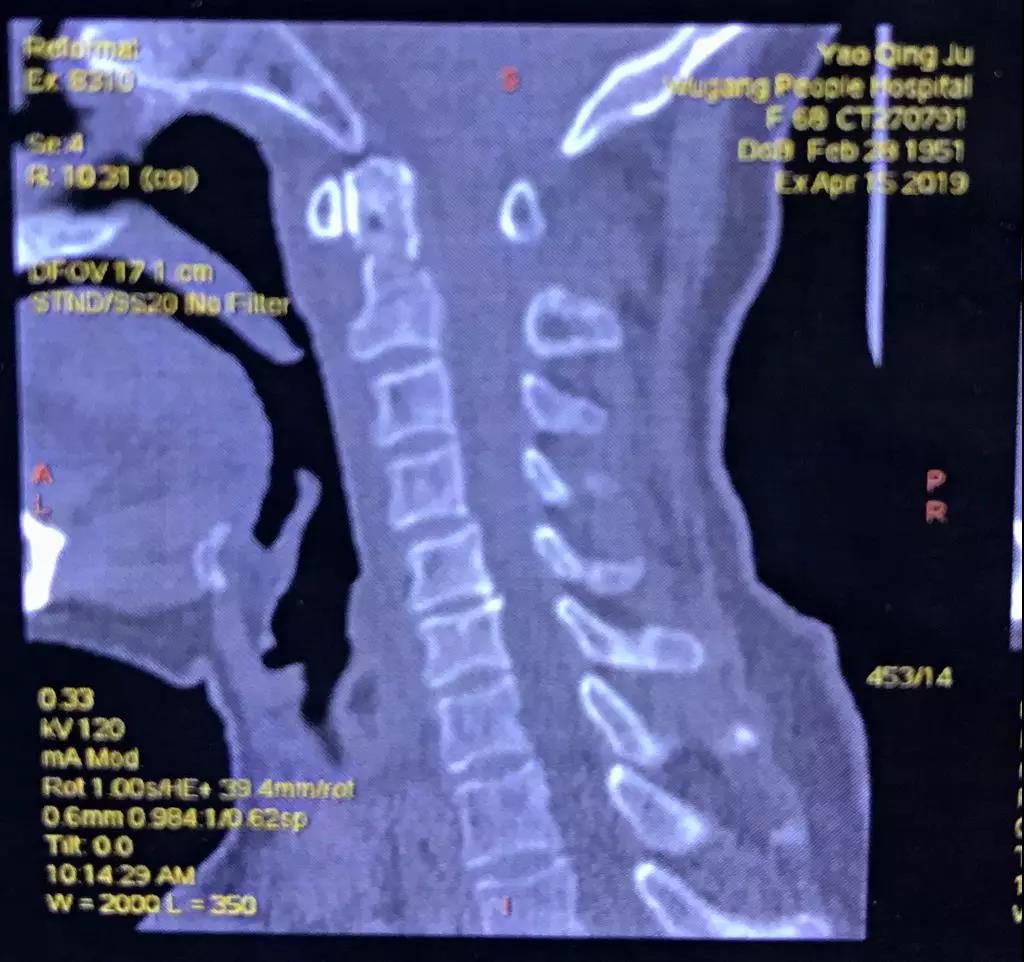

骨卫士特聘专家、原解放军307医院范海涛主任在会上分享了一例C2枢椎齿状突骨折并颈髓挫伤患者病例 。患者为67岁女性,因摔伤致四肢麻木,不能活动。

患者影像资料如下:

▲术前CT